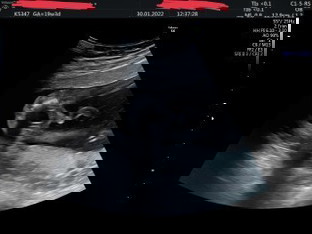

แม่ๆคิดว่าน้องเพศอะไรคะ ที่ยาวๆออกมาคือสายสะดือใช่ไหมคะ

ผู้ชายแน่เลยค่ะ

น่าจะ ผช นะคะ